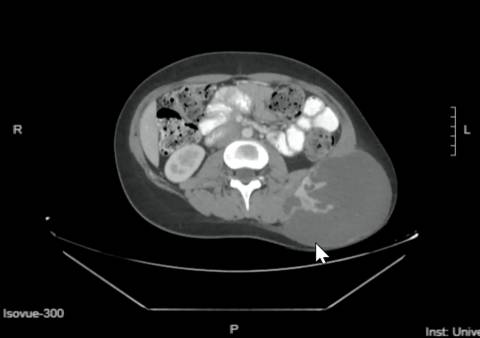

But when a painful lump started to form on the left side of Mya’s lower abdomen in she was referred to a specialist.

A biopsy revealed a 12cm mass diagnosed as spindle cell sarcoma - a tumour that can develop in the bone or soft tissue.